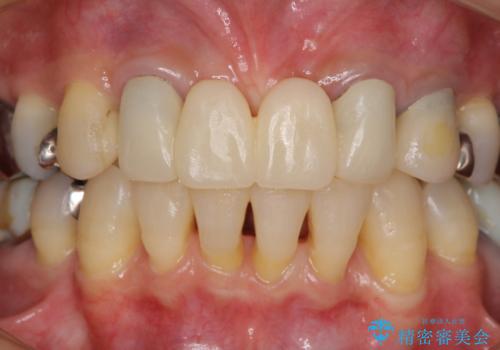

仮歯自体はとても綺麗でしたが、2本の歯が欠損している部分に上唇小帯が入り込んでいたため、歯肉形成を行った上で仮歯を調整し、オールセラミックブリッジを装着することとしました。

他にも治療が必要な歯があったため、合わせてセラミッククラウンやセラミックインレーで治療することとしました。